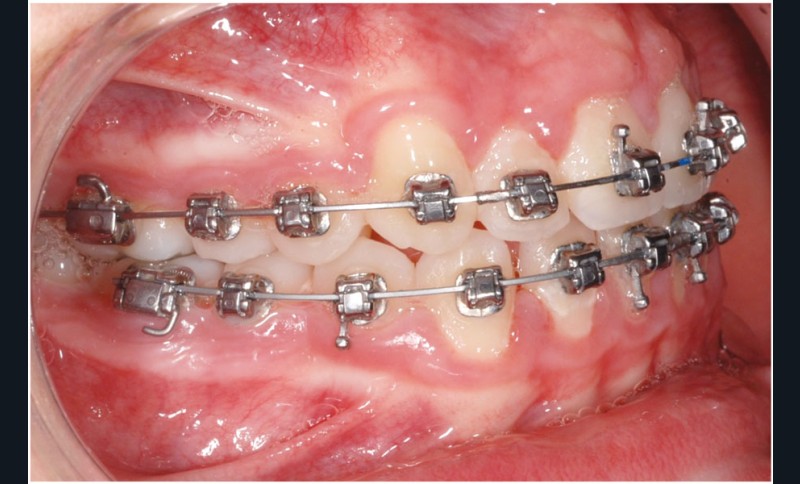

Le cas d’Anthony âgé de 11 ans et 7 mois qui présente une endomaxillie bilatérale associée à un léger encombrement mandibulaire dans un contexte de classe I squelettique hyperdivergente (fig. 1 à 10) est très représentatif de ce que peuvent apporter les forces légères appliquées aux alvéoles dentaires tout en intégrant des torques spécifiques qui permettent de contrôler parfaitement l’orientation radiculaire (fig. 11 à 29).

Le système laisse beaucoup de liberté dans l’interface entre bracket et arc : la vascularisation, et donc le recrutement cellulaire et la reconstruction osseuse s’en trouvent améliorés, la mise en place de l’occlusion se fait sous le contrôle de la matrice fonctionnelle, car les forces engagées restent en dessous de la puissance des forces masticatrices notamment.